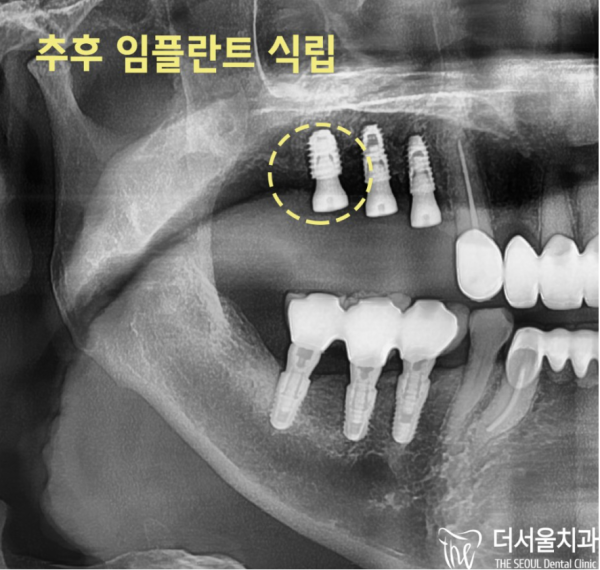

이 환자분은 오른쪽은 어금니 브릿지가 있었고 왼쪽은 어금니 두개가 상실된 상태였습니다.

잇몸뼈가 많이 있지는 않은 상태로 뼈이식이 필요한 상황이었습니다.